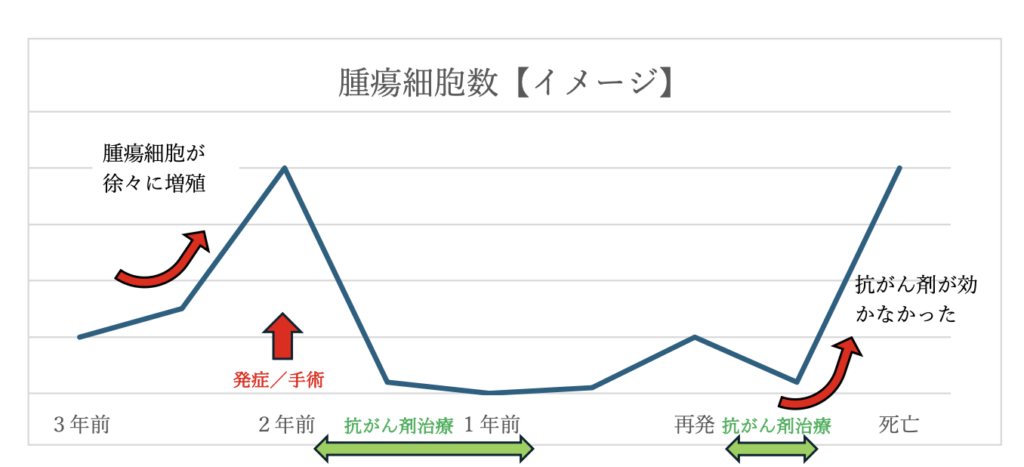

狭窄部位を手術で切除し、残った消化管を繋いで手術は終了しました。病理検査結果は『リンパ腫』。

(2年前にリンパ腫で消化管腫瘤を切除し、その後しばらく抗がん剤治療を経て最近1年間は抗がん剤を終了している状況でのご来院でした。)

2年前のように手術でシコリを手術で切除してみるか、抗がん剤を再開させてみるかを飼い主様と話し合い、抗がん剤の再開を選択しました。

L-アスパラキナーゼという抗がん剤注射を1年ぶりに再開させました。

L-アスパラキナーゼによる治療の4日目から「チュール食べれました!」「爪研ぎできました!」と体調が改善してきました。逆に言うと4日目まではぐったりしていて心配な状況でした。

毎週1回、L-アスパラキナーゼを注射します。6週が過ぎた頃、急に便が出ていない・・・今日から食欲がなくなってきた、とのこと。体重変わらず(便が出ていないから?)でしたが、体温39.0℃の微熱でした。もっとオーナー様との楽しい時間が続くと思っていた最中、体調が悪化し、3日後、天国へ旅立ちました。

症例1及び2は、診断名は異なりますが、『悪性腫瘍』という点と、病理検査にて『進行した病態と思われますので、今後も局所再発、播種性転移、他臓器への遠隔転移など病態の悪化には厳重な警戒が必要と思われます。』との記載がありました。飼い主様にとって耐え難い不安な結果だったと思います。

手術後無治療で6か月を迎えられた症例1のネコさん、手術後抗がん剤も頑張ったのに再発してしまったネコさん、十人十色で診断/治療を行う上で今後の見通しを断言できる症例は少ないのかもしれません。分かることは分かるし、分からないこともしかり。見通しが分からない中でも飼い主様の思いをできるだけ汲み取り、症例の治療に活かしたいと思います。